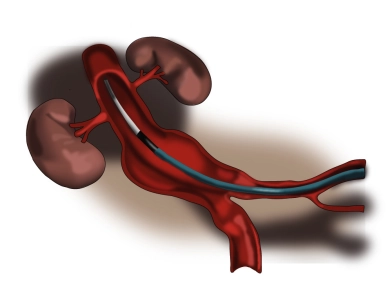

Aorta und Beckenstrombahn

EVAR – Endovaskuläre Versorgung eines abdominellen Aortenaneurysmas (Y-Prothese)